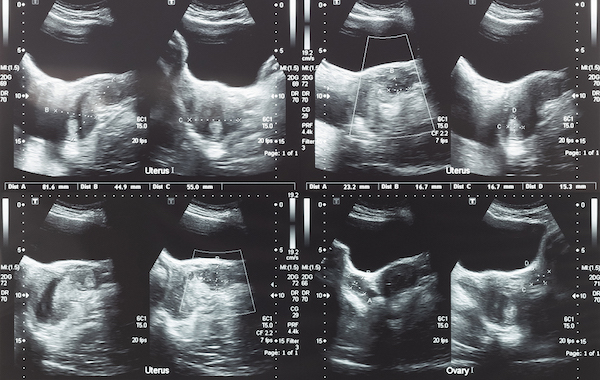

Infertility occurs primarily from the combination of fibroids, ovarian cysts, tubal blockage, and sometimes a hot stomach.

If, by chance, they get in, they’ll struggle with fibroids to gain space to grow.

They’ll also face the womb conditions to get through, and all this would only be possible if the fallopian tubes are open.

Most times, what a lot of health professionals focus on is just the treatment of either fibroid or ovarian cyst.

In fact, during these years of my practice, I have recorded about a 45.9% rate of success with the treatment of gestational fibroids and ovarian cysts.

But one common problem with the above is that 90% of the time, the fibroid grows back and stops you from getting pregnant and having your own baby.

For some, a fibroid can even grow to term, and they deliver it.